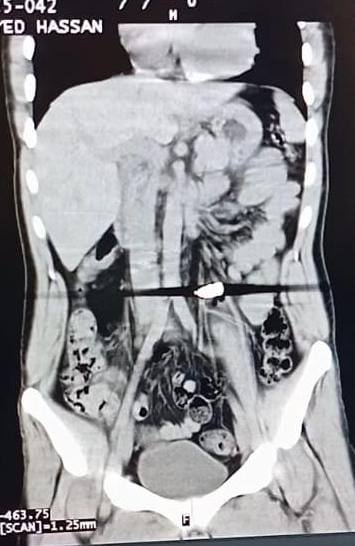

نجح أطباء مديرية الصحة بالإسكندرية، في استخراج طلق ناري لمريض بعد استقراره على بعد 1 سم من الشريان الأورطي.

وذكرت مديرية الصحة بالإسكندرية، أن المريض دخل مستشفى رأس التين العام التابع للمديرية، وكان يعاني من إصابة بطلق ناري بالظهر وإصابة أخرى بالساعد الايسر، مع وجود علامات لنزيف داخلي واحتمالية تهتك بالأنسجة العميقة.

وقام فريقا الجراحة العامة والتجمل بالمستشفى، بإجراء جراحة دقيقة لاستكشاف شامل لمسار الطلق الناري بالظهر والبطن، حيث وجد مستقرا على بعد 1 سم من الشريان الأورطة والحالب الأيسر.

وتم استخراج الطلق الناري بنجاح ووقف النزيف وإصلاح التهتك بالأنسجة المحيطة وإعادة بنائها، وعلاج إصابة الساعد الأيسر، ووضع المريض تحت المتابعة الطبية الدقيقة بعد استقرار الحالة.